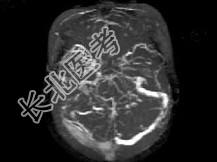

- 单项选择题女,37岁, 产后10天,出现剧烈头痛头昏伴神志不清2天, 根据所提供图像,最可能的诊断是 ( )

A、右侧蛛网膜下腔出血

B、右侧脑膜脑炎

C、右侧硬膜下血肿

D、右侧脑梗死

E、右侧静脉窦血栓形成